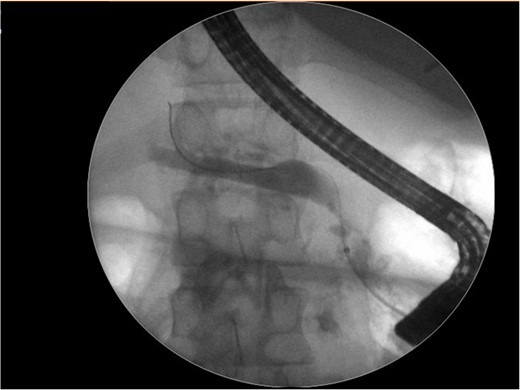

An abdominal ultrasound (Fig. 1), a computed tomography (Fig. 2) and a magnetic resonance cholangiopancreatography (MRCP) resonance showed diffuse dilation of the main pancreatic duct the duct of Santorini and the secondary ducts. Stones inside the main pancreatic duct in the head region, measuring approximately 1.1 cm. Reduction in the thickness of the pancreatic parenchyma, associated with small calcifications in between (Fig. 2).

Abdominal computed tomography shows a diffuse dilation of the main pancreatic duct and Santorini duct, as well as dilation of secondary ducts. There are stones in the main pancreatic duct in the head region. Also, there is a reduction in the thickness of the pancreatic parenchyma, associated with small intervening calcifications, possibly due to chronic pancreatitis.